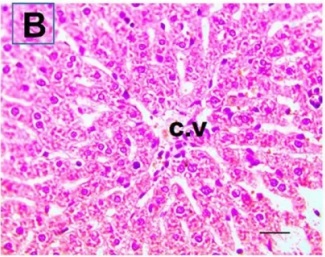

Put the liver tissue section under a microscope, and you can see that cisplatin can cause liver congestion (the blood that should return to the heart is blocked and stagnates in the hepatic veins), cell degeneration (vacuoles appear, which is the earliest change in cellular injury), apoptosis and necrosis, but these conditions can also be alleviated by using Ganoderma lucidum.

Figure 2 Effects of cisplatin and Ganoderma lucidum on hepatocytes